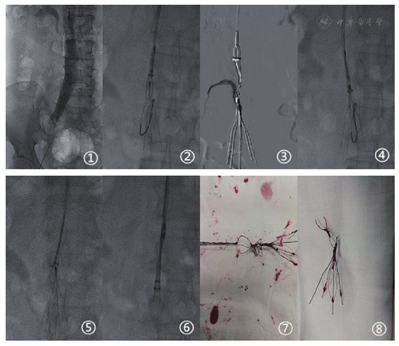

入院后第5天,行下腔静脉可回收滤器取出术。经双侧足背静脉留置针造影示:双下肢静脉未见充盈缺损。Seldinger法穿刺右股静脉成功后送入4F短鞘,经鞘造影示下腔静脉通常,滤器贴壁(图1),泥鳅导丝配合4F多功能导管选入下腔静脉,交换入260 cm超硬泥鳅导丝于滤器上方,纠正滤器倾斜贴壁。Seldinger法穿刺右颈静脉成功后,置入5F短鞘,泥鳅导丝配合4F多功能导管选入下腔静脉远端,交换260 cm超硬泥鳅导丝,沿导丝送入9F短鞘扩张右颈静脉穿刺点,后沿导丝送入BARD圈套器取回套组于下腔静脉滤器上方。抓捕器反复尝试抓捕滤器上方小钩未成功,但与断裂滤器细丝缠绕(图2,图3,图4),无法收回抓捕器。退出9F取回鞘,260 cm超硬导丝配合切除部分头端的Pigtail导管沿11F导引鞘软管送入,到达滤器下方,继续沿导引鞘送入Atrieve抓捕器于下腔静脉滤器上方,成功抓捕260 cm超硬泥鳅导丝软头,退出Pigtail导管后,将导丝拔出体外。收紧260 cm泥鳅导丝双侧头纠正滤器倾斜贴壁,经导引鞘送入Atrieve抓捕器,成功抓获滤器上方小钩。沿三条导丝送入取回鞘,收紧导丝,将滤器收入鞘内,拔除体外,见滤器完整,断裂部分与BARD抓捕器紧密缠绕(图5,图6,图7,图8)。重复造影示:下腔静脉显影良好,未见对比剂外溢。术后复查腹部CT未见下腔静脉异常。